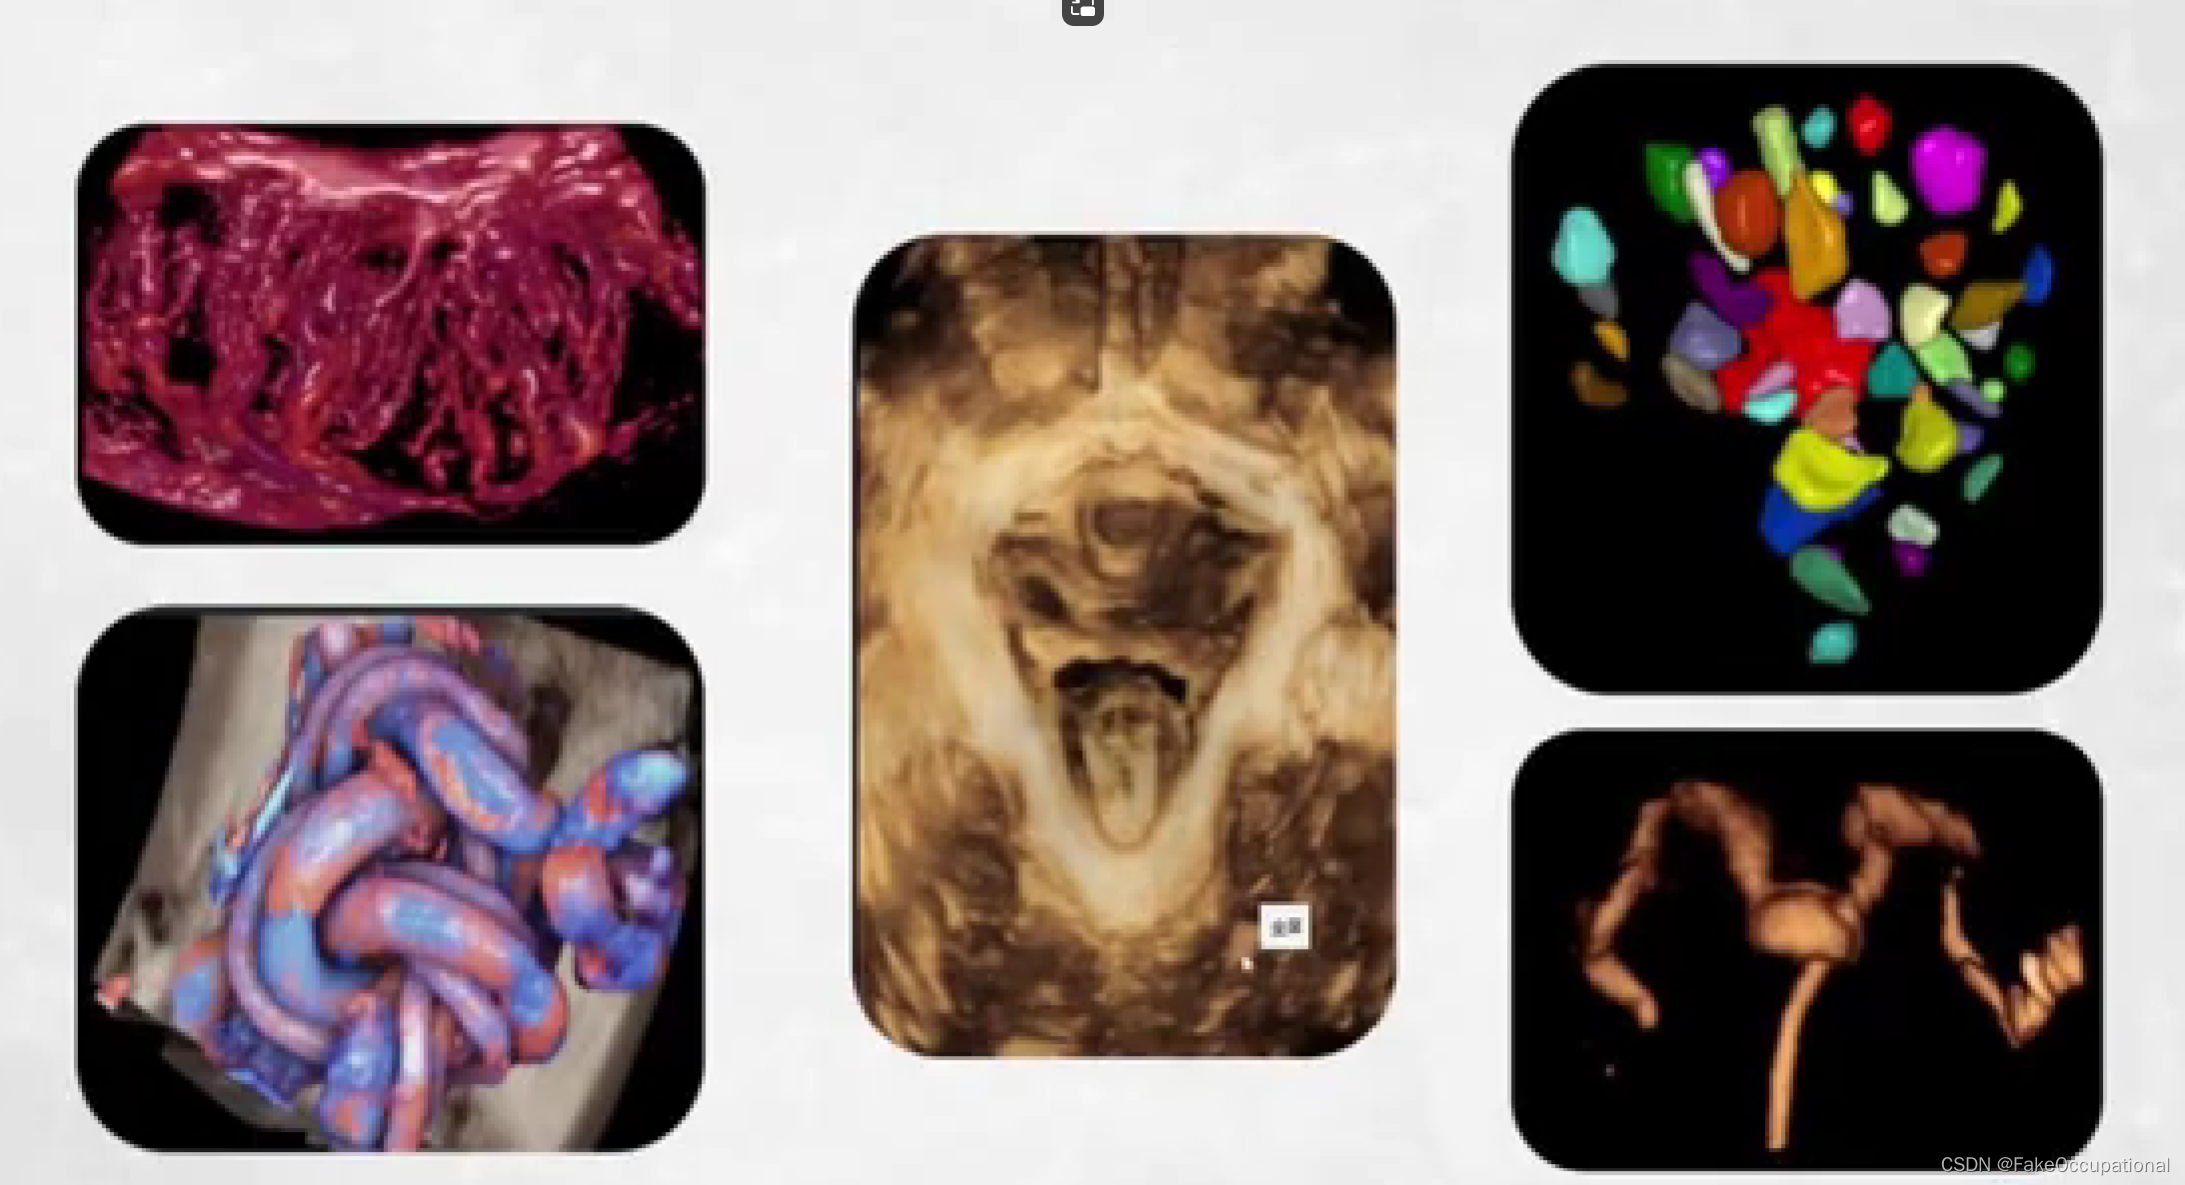

超声新技术

1.三维超声

2.超声造影

3.弹性成像